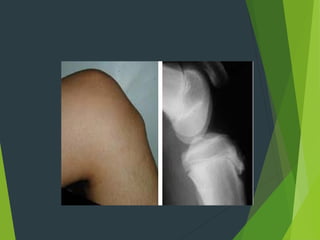

Osgood schlutter`s disease :

It is osteochondritis of upper tibial tubercle ,affecting children

8-15 years old .

The tibial tuberosity become swallown , tender and extension

of the knee joint against resistant is painful .

X-ray : show irregular fragmentation of apophysis in which

infra patellar tendon is inserted .

Osgood schlutter`s disease: It is osteochondritis of upper tibial tubercle ,affecting children 8-15 years old . The tibial tuberosity become swallown , tender and extension of the knee joint against resistant is painful . X-ray : show irregular fragmentation of apophysis in which infra patellar tendon is inserted . Treatment : spontaneous recovery is usually occur and it is necessary to modified child activity e.g., stop plying foot ball and stop cycling . If pain persist then put in plaster cylinder for about 1-2 months occasionally excision of the fragmented piece by operation is done